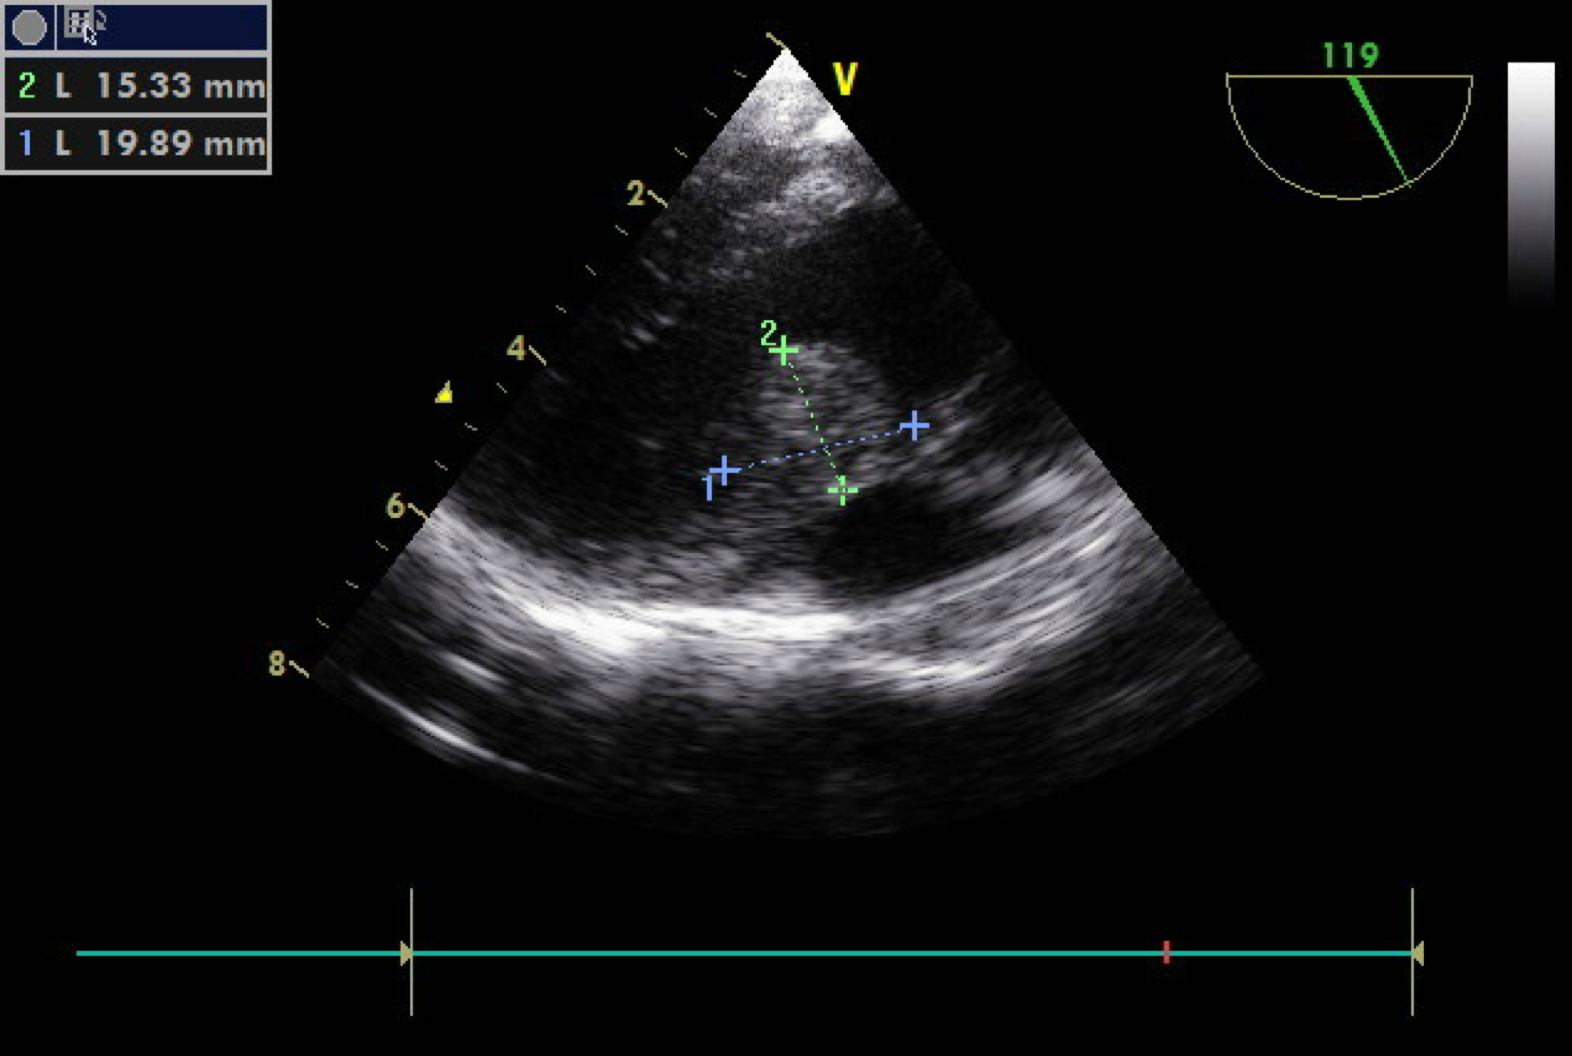

心肌梗死脆弱期心腹痛首次发作后1个月内发生心肌梗死的可能性达59%。不稳定型心腹痛不稳定型心腹痛44%~70%发展为急性心肌梗死心源性猝死的三个原因,16%发生身亡。陈旧性心肌梗死陈旧性心肌梗死并室壁瘤,可再度或多次发生中风,心肌梗死后6~18个月为危险期。高血糖伴左心室肥厚出现无病症心肌缺血,应提防心源性身亡。特点性心电图改变如ST段缺血性低血糖,ST段显著抬升及T波直立耸立,巨大U波,双束支传导阻滞,严重心动过缓等。老年心源性身亡救治成活的患者其二年内恶变率达30%~40%,应提防再度身亡。5、诊断手段大多数患者应当进行全面的心肌功能评价和冠状动脉解剖结构检测。超声心动图检测对肥厚性心肌病和瓣膜性肾脏病在内的疾患很有用;核磁共振检测对有心率失常性右室发育不良症的确诊很有用;心肌造影对浸润性疾患如心肌炎、淀粉样变、结节病很有用。应进行冠状动脉血管活检评估冠脉阻塞性疾患的存在并排除冠脉的结构异常。心肌灌注闪动照相对缺血程度恐怕可提供辅助资料。通过对比心室活检、同位素心室活检或超声心动图可以了解左心室功能。对心源性身亡生还者的测试也包括动态心电图监护仪和/或电生理测试。6、预防建议防止过度激动、紧张要节制情绪变化,切勿大喜、大怒、大悲等情绪。